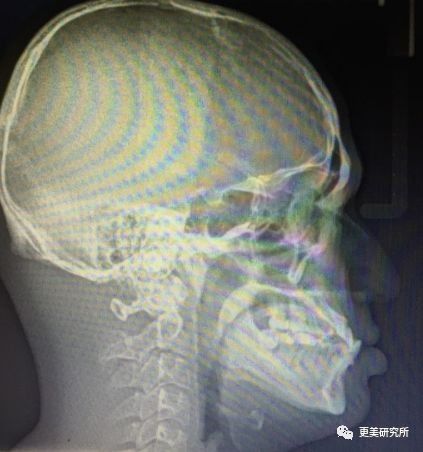

出现骨性地包天主要是因为下颌骨发育过度前突导致的,这个问题需要做正颌手术+牙齿矫正(具体是哪种肉眼是无法判断的,所以大家别想偷懒,还是去医院拍个片子吧)

牙性地包天、轻微的骨性地包天一般戴牙套就可以解决,严重的话就需要做正颌手术了。

在正颌手术过程中,医生会截掉部分下颌骨,并且把发达的上颌骨后移,让上下牙的咬合恢复正常。